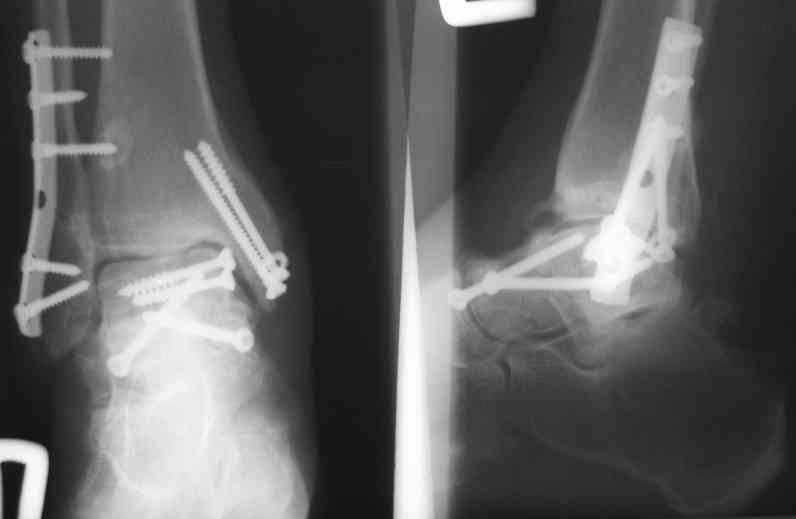

Случай с множественным оскольчатым переломом тарана оперированный из двойного доступа.

Через 2 мес.:

Через 8 мес.:

Через 14 мес.:

Решили не связываться с остеосинтезом, а сделать сразу берцово-пяточный блок. Снимки в приложении.

По завершении удлинения, наверно, заштифтуем.

Комментарии/критика приветствуются.